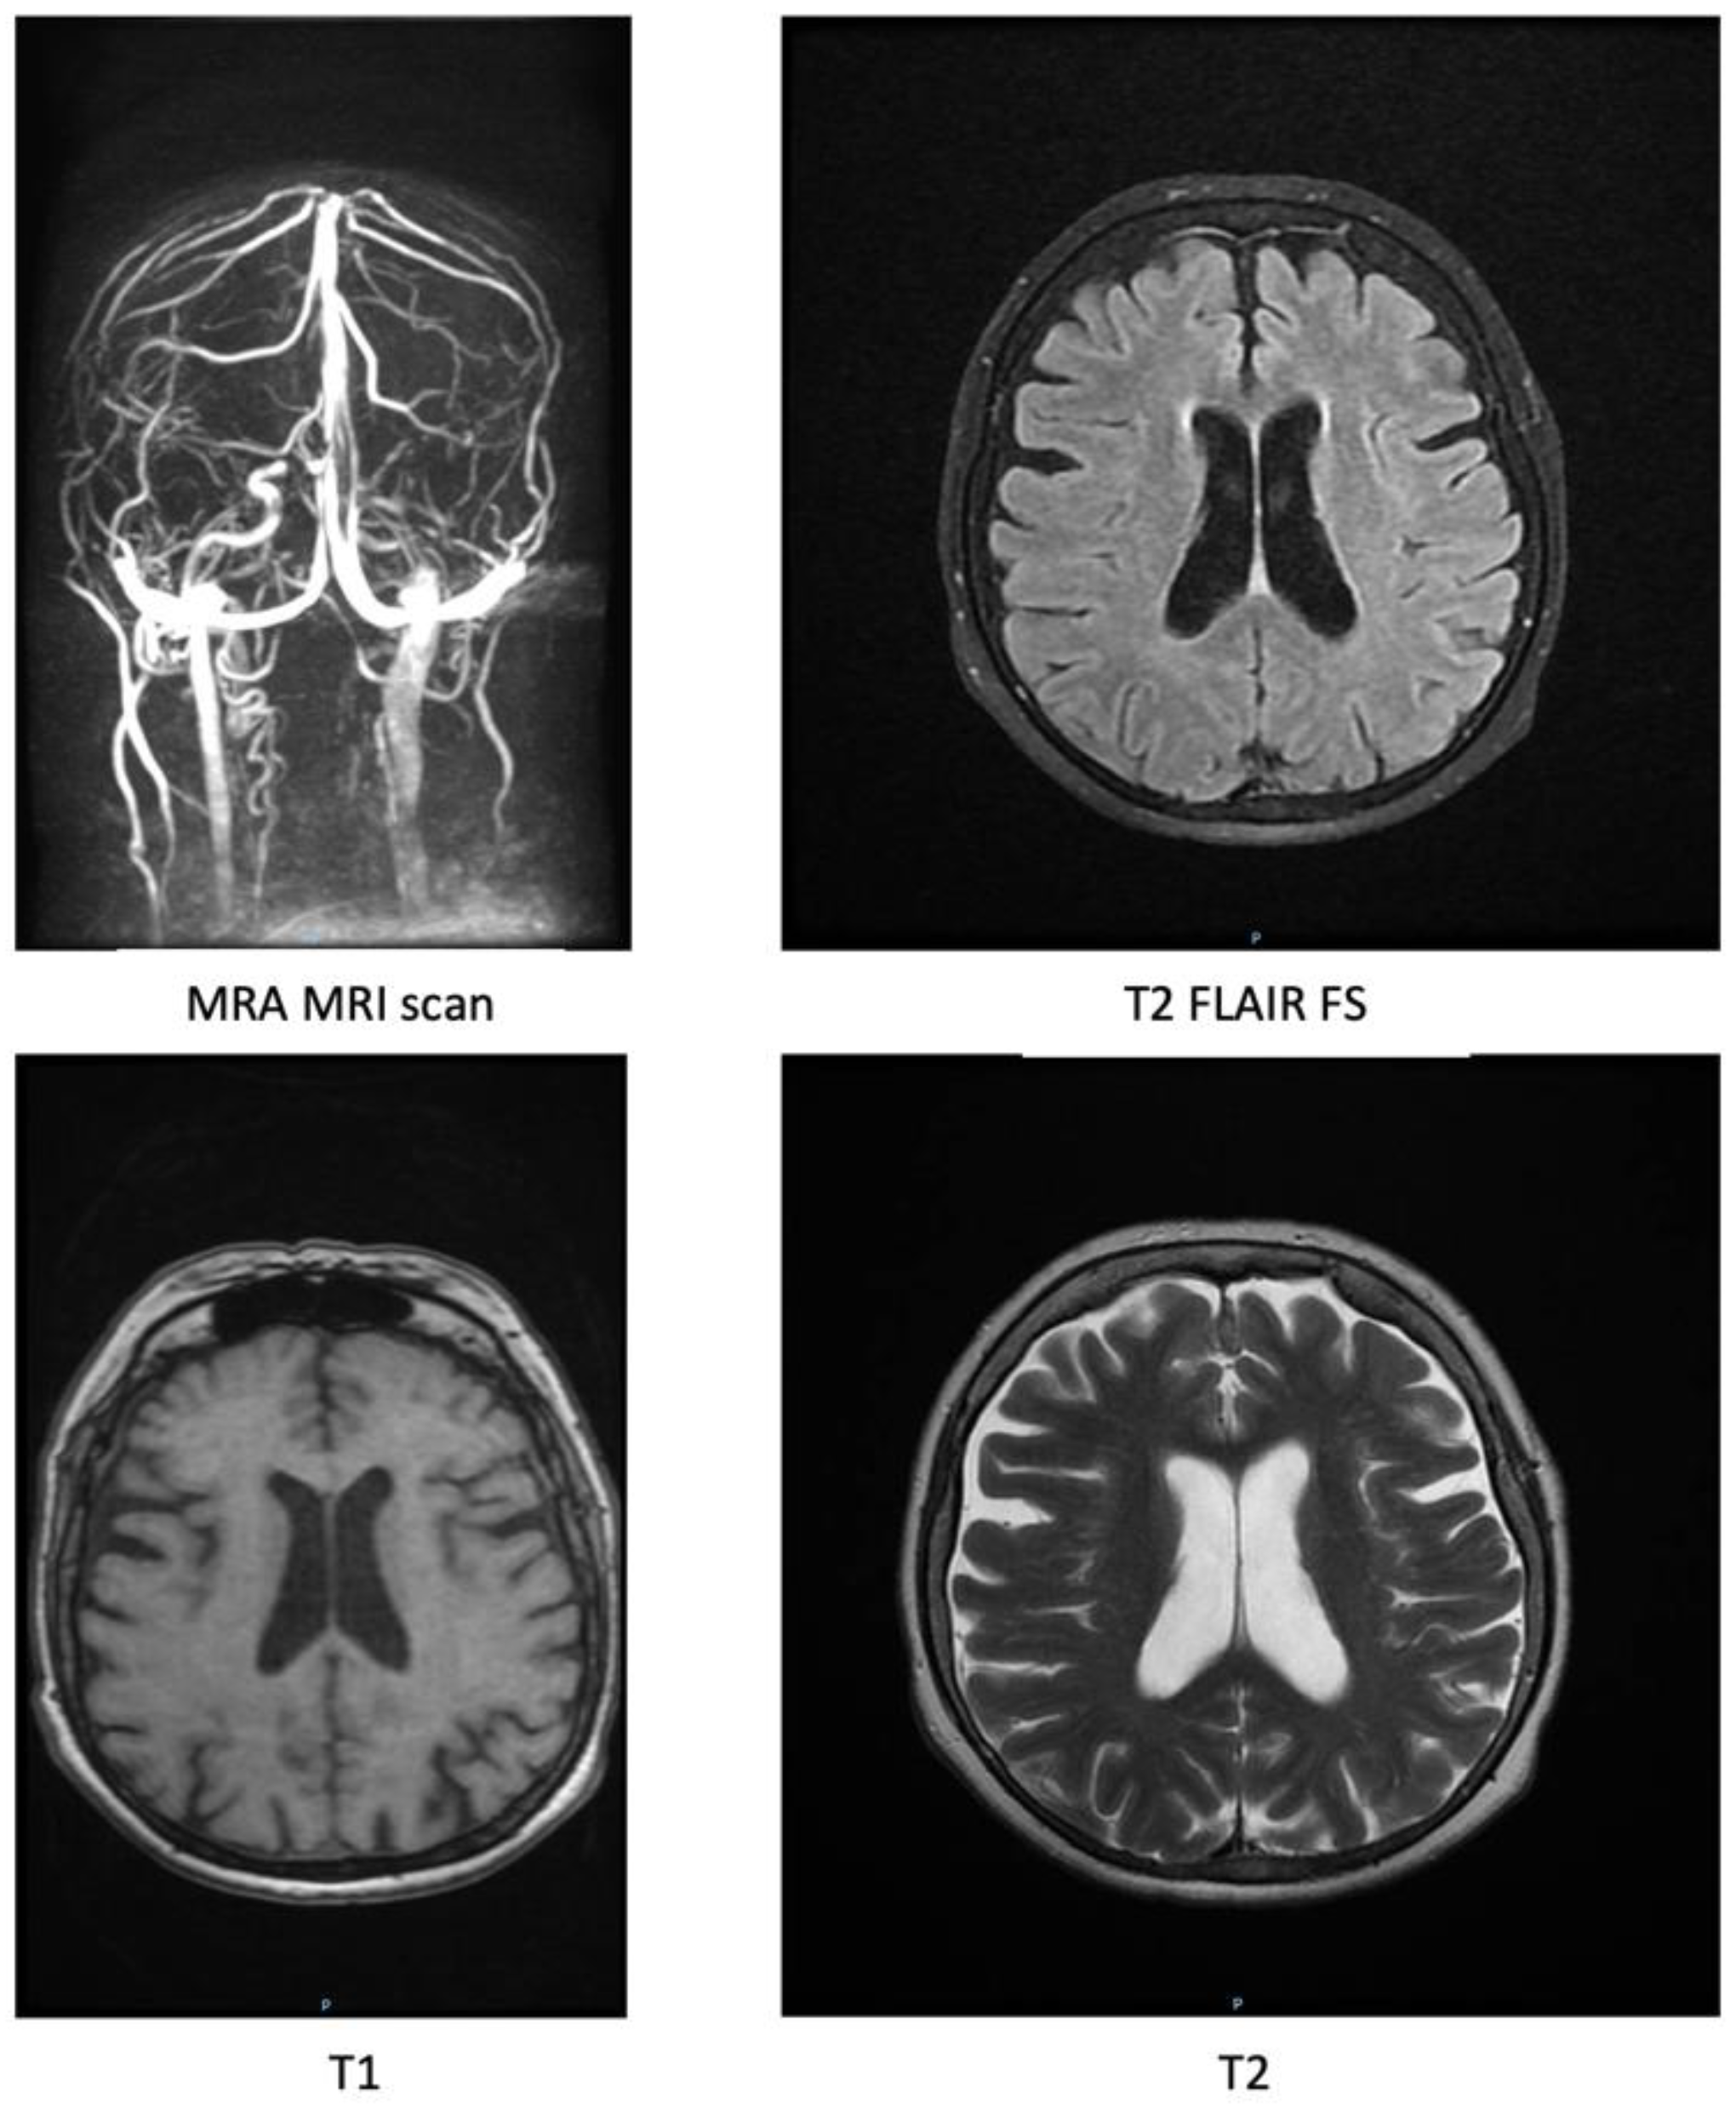

A rapid-sequence cranial magnetic resonance imaging (MRI) and magnetic resonance angiography (MRA) were also performed. Under subject motion artifacts conditions, the following results were reported: symmetrical cortical relief with wide cortical and cerebellar grooves and a deep Sylvian fissure. Midline structures with normal topography. The symmetrical ventricular system was located on the midline, slightly compensatory dilated, and had normal pressure. No areas of focused edema or mass edema, no restriction in diffusion sequences, no blood degradation products in magnetic susceptibility sequences, a non-specific frontal demyelinating lesion, non-restrictive, and with a diameter of about 5 mm, with vasculo-degenerative substrate. The 3D time of flight angiography sequence highlights a sinuous trajectory in the V4 portion of the vertebral arteries and in the basilar arteries, without other abnormalities of trajectory, caliber, or flow in the cerebral arterial system. The 2D time of flight angiography sequence does not show abnormalities in trajectory, caliber, or flow in the vessels of the cerebral venous system. Orbits, optic nerves, chiasm and optic tracts, pituitary gland, and internal auditory canals had a normal MRI appearance. The sequence with thin sections of the base of the skull did not highlight any pathological or signal abnormalities in the cranial nerves. Hypertrophy of the mucosa of the middle and lower right nasal conchae was noted; a right-deviated nasal septum. In conclusion, cerebral atrophy and right-deviated nasal septum were observed.

Figure 2. Magnetic resonance imaging scan sequences.